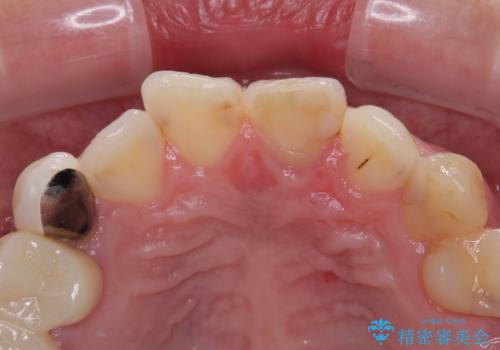

- むし歯により神経を取り除く処置をした歯と隣接する歯の捻れを気にして来院された患者様です。

神経を取り除いた歯は変色が始まっており、隣の歯は捻れにより突出している印象であったので、前歯2歯をオールセラミッククラウンにて補綴することとしました。

捻れている歯は、神経が露出する可能性があり、その場合には根管治療が必要となります。